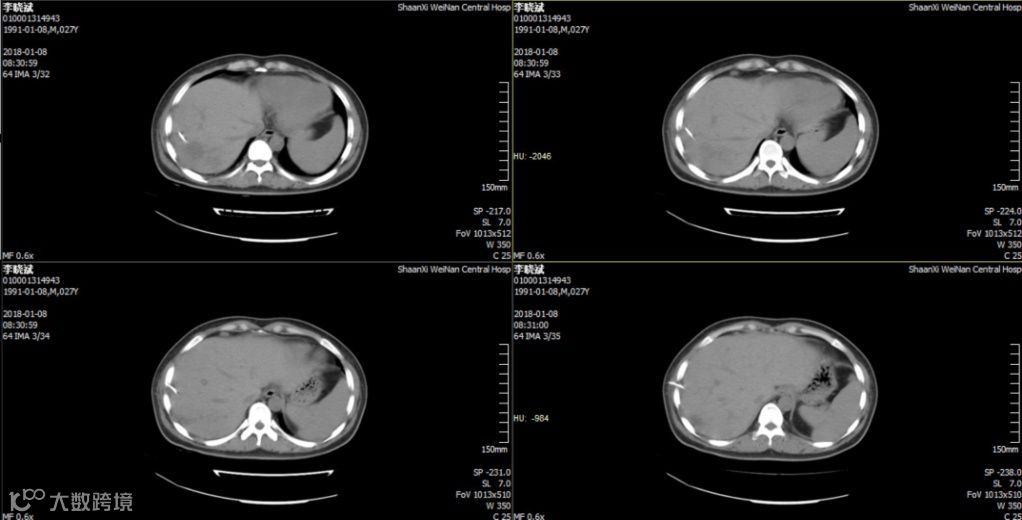

2018.11.25复查CT:双肺炎症,考虑特殊细菌感染可能,双侧胸膜腔少量积液,心包少量积液,腹腔少量积液,少许游离气体,部分包裹,肝右叶、脾实质混杂密度包块,脓肿并气体。因经济原因换用头孢曲松 2.0 g,QD,ivgtt。12月8日再次发热,12月12日肝脏穿刺引流后体温逐渐正常,CT提示病灶逐渐吸收。

KPLA有如下特点:血糖控制不良;主要表现:畏寒、发热,乏力,血象高,血红蛋白和血浆白蛋白下降;局部定位症状不典型,明显右上腹痛、肝脏肿大及黄疸不多见;局限于肝右叶的单发病灶为主,这可能与肝右叶体积较大以及血液较多有关;脓肿内可出现气体,与高糖条件下Kpn发酵组织中的葡萄糖产生二氧化碳有关; 预后良好,病程不如其他类型细菌性肝脓肿凶险。